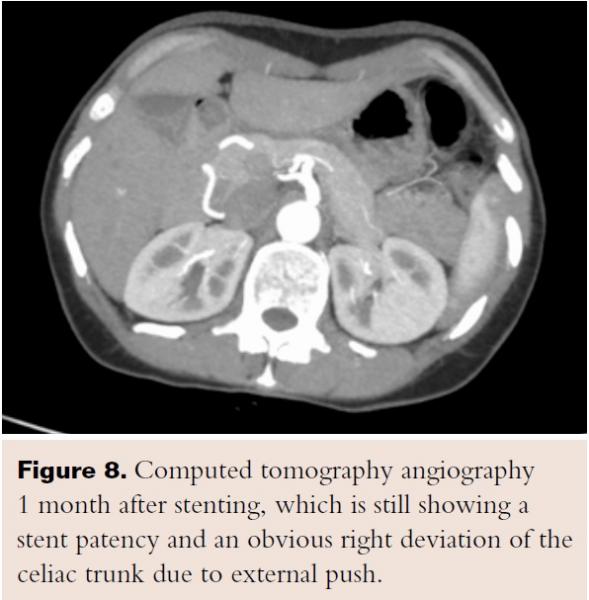

Given her age and co-morbid disease, the patient’s risk stratification was high for a moderate-to-high risk procedure; the patient was judged to be a poor surgical candidate and so the decision was made to refer her to interventional cardiology for consideration of less invasive treatment. A selective angiography of the celiac trunk was performed via the right common femoral artery with a 6 Fr system. During angiography, both inspiration and expiration films were compared; celiac artery stenosis was more prominent during expiration, and a characteristic superior indentation was noted along the proximal celiac axis (Figure 2), which led to the confirmation of MALS diagnosis. The celiac trunk was engaged with a 5 Fr, 0.035˝ Slip-cath VS 80 cm (Cook Medical), and the lesion was crossed with a 0.035˝ guidewire (Boston Scientific). Percutaneous transluminal angioplasty (PTA) of the proximal celiac trunk was performed with a 6.0 x 20 mm Mustang balloon (Boston Scientific). As expected, there was no significant angiographic improvement, so a 5.0 x 22 mm Cast stent (Atrium Medical Corporation) was deployed at 4 atm and postdilated at 10 atm. Final angiographic results showed reduced narrowing from 90% to 0%. IMA and SMA were patent (Figure 3).